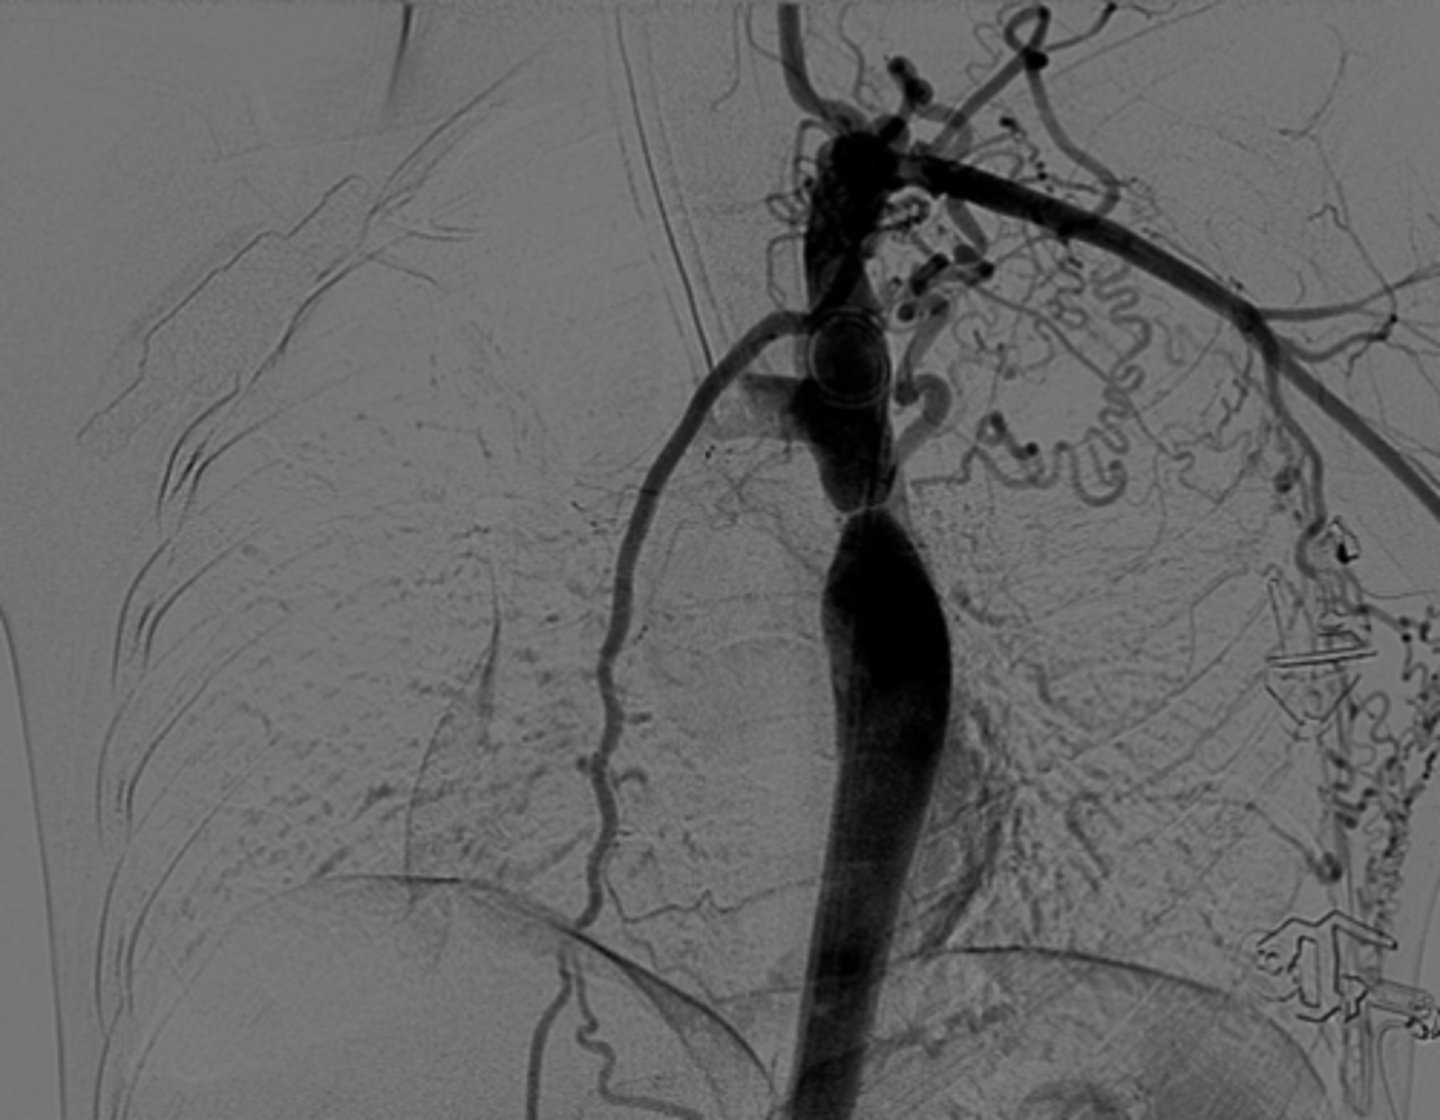

What are the key features of adult coarctation of the aorta?

Narrowing opposite a closed ductus arteriosus, distal to the great vessels from the aortic arch.

What causes dysphagia lusoria?

Abnormal origin of the right subclavian artery results in compression of the esophagus -impairment of swallowing